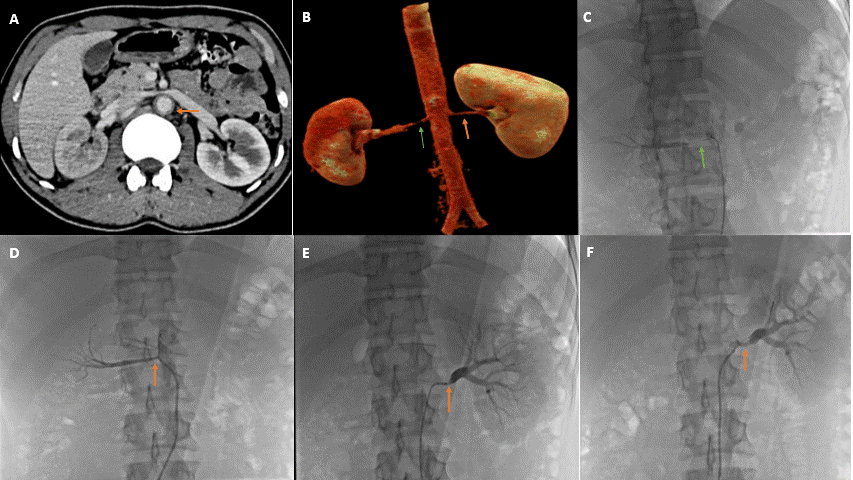

Computed tomography angiography of the abdomen revealed bilateral renal artery stenosis with 99% stenosis in the right renal artery and 90% stenosis in the left renal artery, with thickening of the abdominal aorta (Figure B) and the “double ring sign” (Figure A). A diagnosis of Takayasu arteritis type IV was made. Renal angiography confirmed the findings (Figure C and E) and, subsequently, the patient underwent bilateral renal angioplasty with a cutting balloon and a drug-coated balloon. The end result of the procedure was satisfactory with mild residual stenosis (Figure D and F) and a significant improvement in blood pressure. The patient was well controlled on a single antihypertensive at the 2-month follow-up.

Takayasu arteritis is an idiopathic, large vessel vasculitis affecting the aorta and major branches. It has the highest affinity for the left subclavian artery; however, in the Indian population, abdominal aorta involvement is more common. The “double ring sign” is an important sign and marker of active disease (showing a hyperenhancing outer ring due to thickening of the medial and adventitial layers due to inflammation, and a hypo-enhancing inner ring due to swelling of the intima and luminal narrowing). In light of ongoing disease activity and fear of stent restenosis in this case, stenting was deferred, and the patient underwent ballon angioplasty with acceptable results.